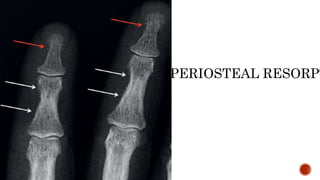

FINDINGS

 Osteopenia

 Subperiosteal resorption: classically along radial aspects of phalanges

SUBPERIOSTEAL RESORPT